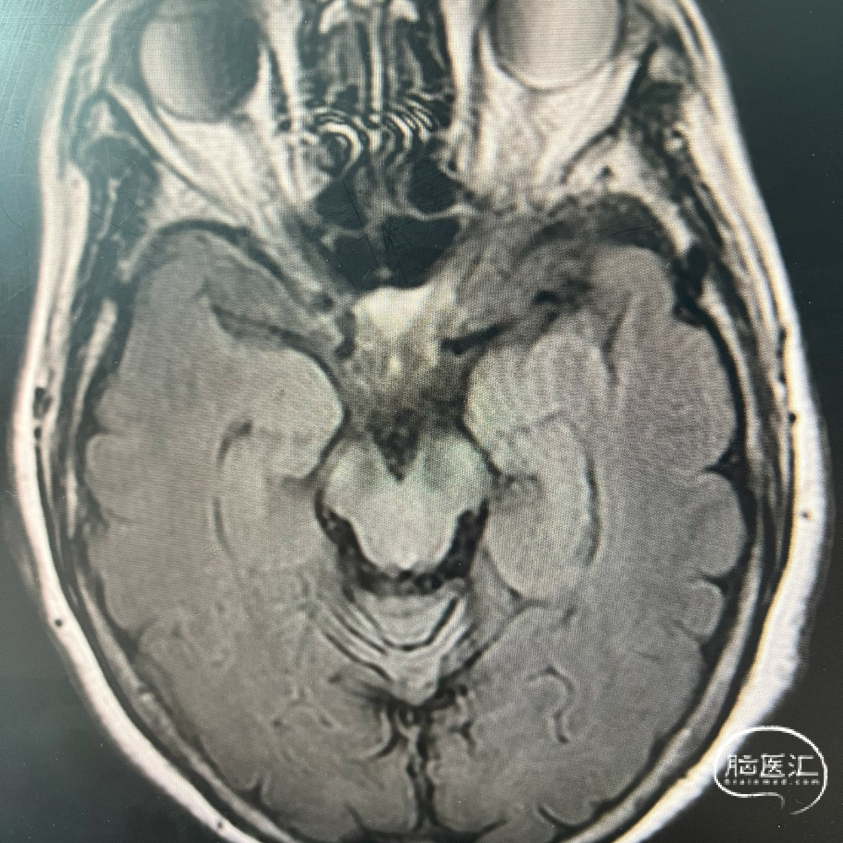

病例信息

患者:74岁,女性。

主诉:头晕20天,伴行走不稳1天。

现病史:患者于20天前无明显诱因出现头晕,坐起、平卧及转动头位时发作,自觉天旋地转感,伴恶心,症状持续约数秒钟缓解,无呕吐、视物重影,无吞咽困难及饮水呛咳,无言语不利,无耳鸣耳堵耳胀,无肢体麻木无力等,症状间断发作,在当地医院输液治疗(具体不详)后症未见好转。1天前患者出现行走不稳走路左偏,伴有双下肢乏力,无肢体麻木,为进一步诊治来我院门诊就诊,以"头晕待查"收入我科。

既往史:高血压病史10余年,血压最高160/100mmHg,否认"冠心病、糖尿病"史,否认食物、药物过敏史。

术前诊断:

基底动脉狭窄(重度)

大脑动脉血栓形成引起的脑梗死

高血压病2级(很高危)